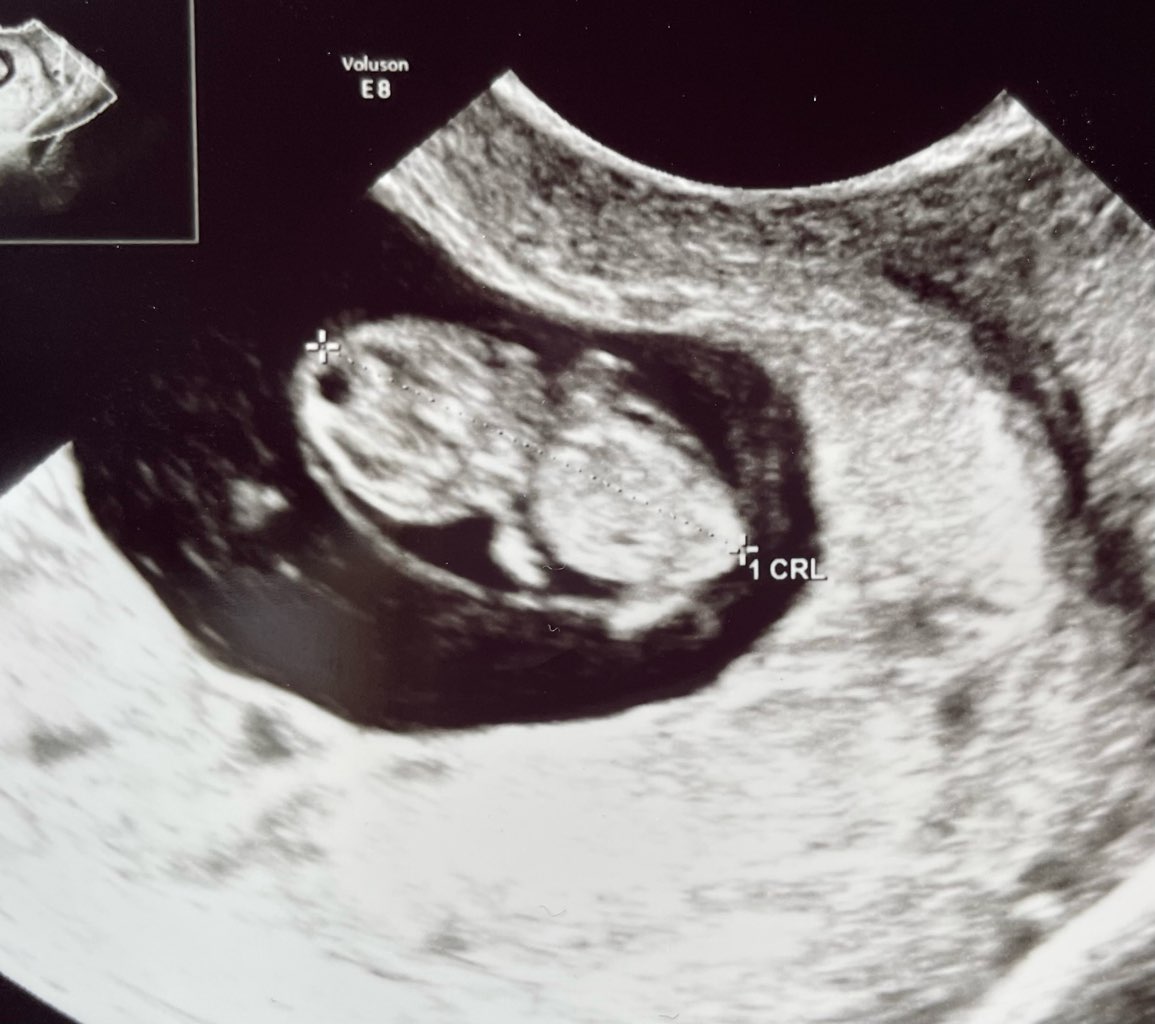

Ja chyba będę jedna z pierwszych rodzących, bo termin z dzisiejszej wizyty mam na 2 października, wychodzi dzisiaj 8+5 :)

Kruszynka ma już 2cm i serce bije mocno, wszystko OK:)